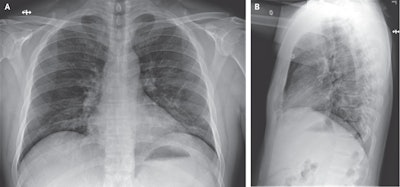

However, x-ray images obtained on the evening of the fifth day of hospitalization (ninth day of illness) showed evidence of pneumonia in the lower lobe of the left lung, which coincided with the patient's progressively worsening respiratory status and oxygen saturation values.

By hospital day 6 (10th day of illness), a follow-up x-ray exam revealed basilar streaky opacities in both lungs, consistent with atypical pneumonia. The patient's clinical condition improved after treatment with oxygen supplementation and antiviral therapy, though he remained hospitalized at the time of publication.